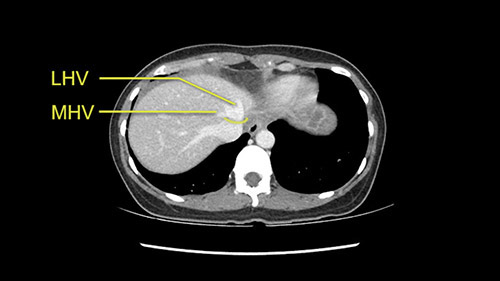

The transection line will be a little more obvious. There’s a little patch of focal fat here in Segment 4b but we’ll describe the transection line probably through the mid portion of Segments 4a and b up to the top. Up at the top, the left hepatic vein can be taken. There’s a Segment 3 vein or the so-called falciform vein it’ll be rudimentary so I think we’ll be able to get around the left hepatic vein and leave the middle [hepatic] vein intact because it’s free of tumor.

Her vein, it looks like a combined middle and left hepatic vein, it may be encircled during the case as a whole common trunk but most probably it will not be a big deal because if it is okay to go with the left lateral resection, the vein or the left hepatic vein can be catched during the intraparenchymal dissection and can be controlled in that side.

The cava however is again displaced by this well encapsulated mass, so I would expect that I should be able to lift out of the cava with some moment of careful dissection and the cava is not infiltrated by this tumor. Most of the tumor is below the portal plane and the hepatic-venous vein is completely free. You have the left and the middle hepatic vein joining together and opening up. The right hepatic vein is as usual. All the superior segments of the liver are intact so we do not expect any major problem in this particular case as far as the venous outflow is concerned. So this is about the preoperative planning as far as this case is concerned.

The other option of course is to do an anatomical left hepatectomy. In that case, I will start mobilizing of course the left lobe and try to find the ligamentum venosum, take it down and go around the left hepatic vein. I think, importantly in these cases and in this case, as you can see in the venous phase, that’s clearly a moment to stop. Because the left hepatic vein is pretty close to the middle hepatic vein as sometimes it is so you may need to dissect a little bit the parenchyma on top of the left hepatic vein to be able to go around the left hepatic vein safely.